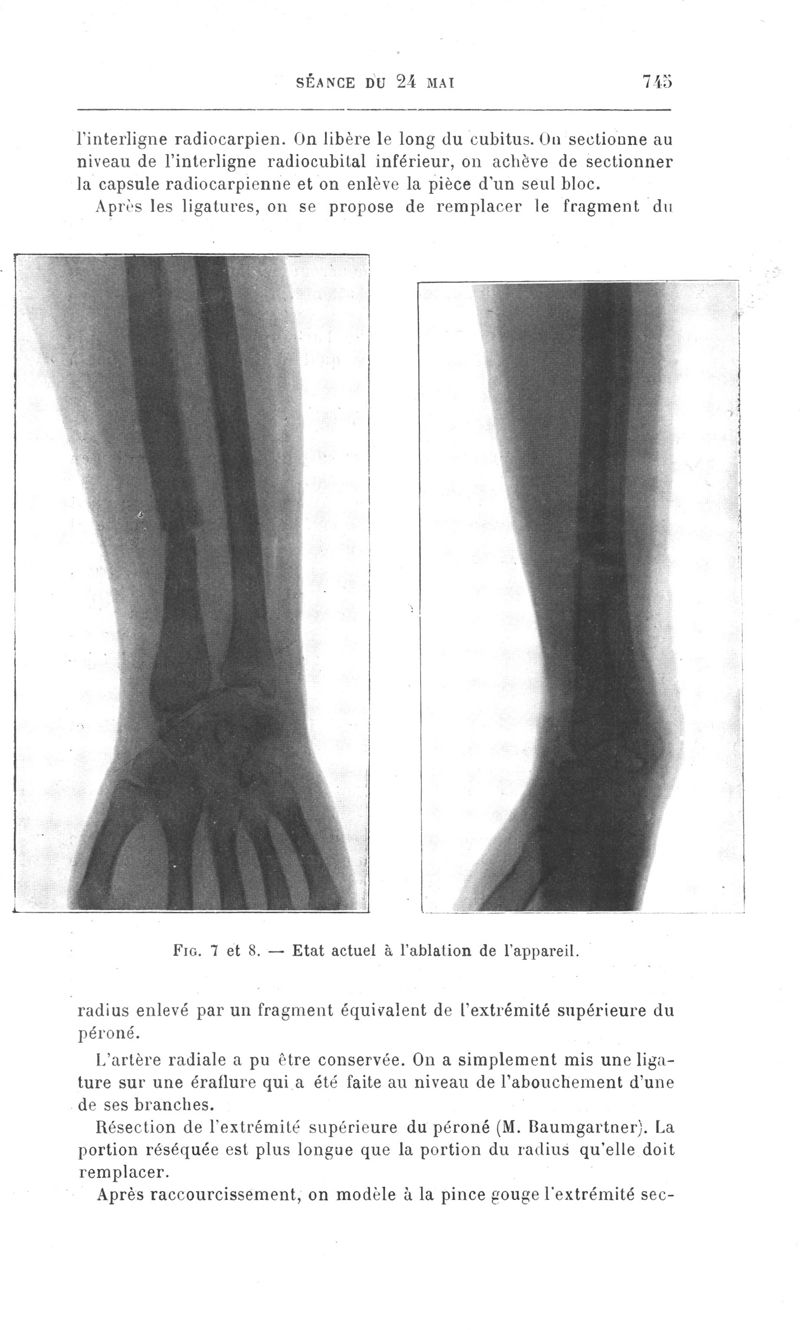

Bulletins et mémoires de la société de chirurgie de Paris

Tome XXXVII, 1911. - Paris : Masson, 1911.